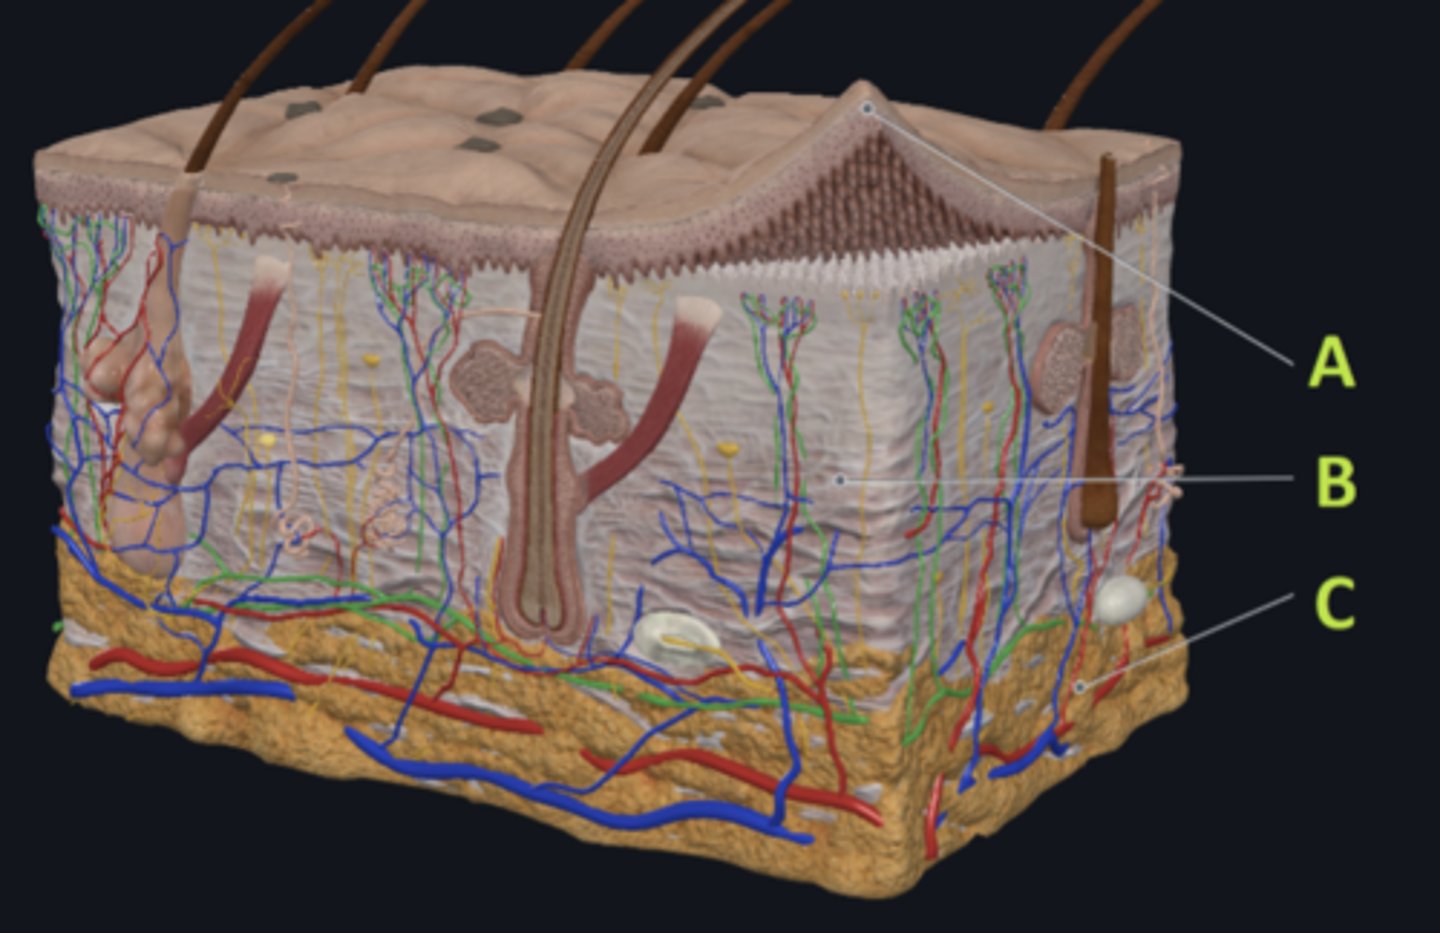

C - hypodermis

Answer the following questions based on the features indicated in the following image. Which letter indicates the administration site for subcutaneous injections?

A - epidermis

Answer the following questions based on the features indicated in the following image. Which letter indicates the administration site for topical creams and ointments?

B - Dermis

Answer the following questions based on the features indicated in the following image. Which letter indicates the administration site for the tuberculin skin test?

A - epidermis

Answer the following questions based on the features indicated in the following image. Which letter indicates a region of the skin with no nerves or blood vessels?

B - Dermis

Answer the following questions based on the features indicated in the following image. Which letter indicates the region where skin appendages (sweat glands, sebaceous glands, and hair follicles) have their roots?

Epithelial tissue

Answer the following questions based on the features indicated in the following image. Which of the four major tissue types is indicated by letter A?

Which letter indicates the administration site for insulin injections?

A

Which letter indicates the administration site for a lidocaine patch?

B

Which letter indicates the administration site for an allergy test?

B

Which letter indicates a region of the skin rich in dense, irregular connective tissue?

C

Which letter indicates the region most important for energy storage and thermal insulation?

Connective

Which of the four major tissue types is indicated by letter C?